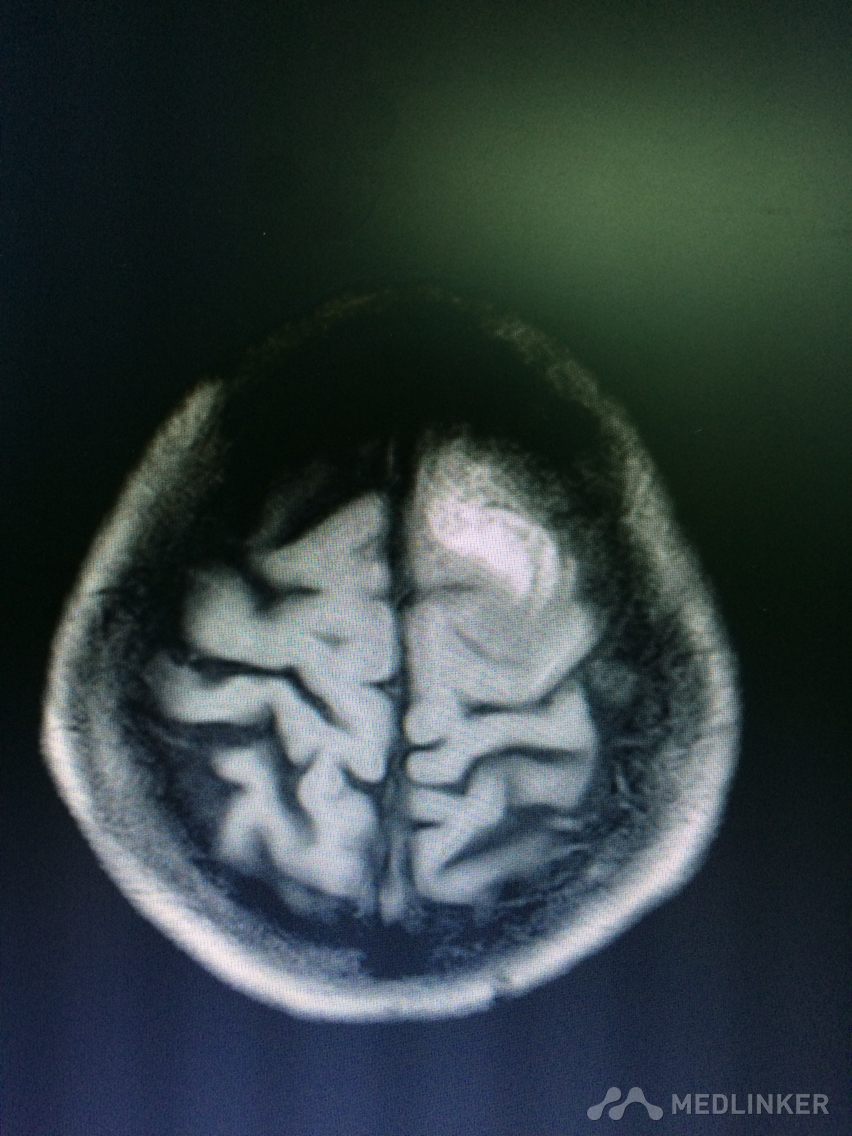

看看这MRI,奇怪啊,快来帮忙看看?

患者78岁老年女性,以精神行为异常和认知障碍为主要表现